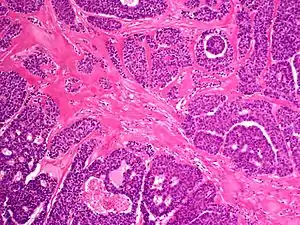

Malignant acrospiroma

A malignant acrospiroma is a sweat gland carcinoma of the hand, which may recur locally in 50% of patients after excision, with distant metastases occurring in 60% of patients.[2]